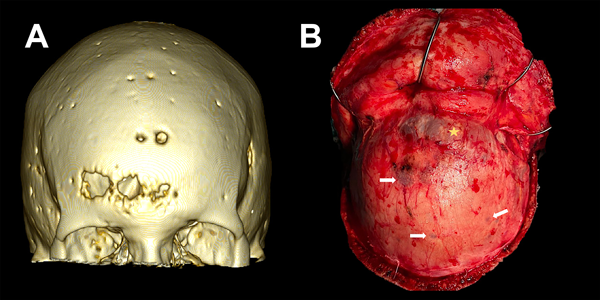

Figura 3. Lesiones osteolíticas con componente exofítico transcraneano. A) TC con reconstrucción 3D de ventana ósea donde se evidencia calota erosionada por lesiones en sacabocado, características del mieloma múltiple. B) Correlación intraquirúrgica de lesión osteolítica y exofitica (estrella amarilla). Presencia de múltiples lesiones en sacabocado a nivel de la calota craneana (flechas blancas).